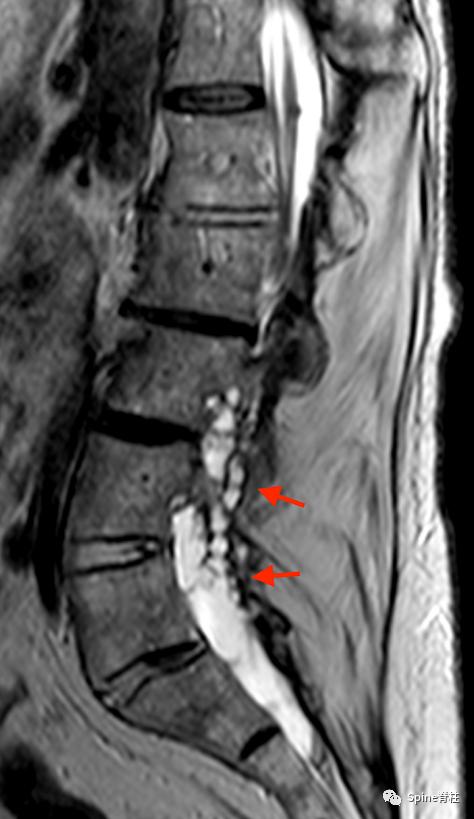

一名20 岁男性1型神经纤维瘤病患者出现背痛和下肢感觉障碍,肌力正常。随后,他出现尿潴留,感觉平面下降至 T10 水平。影像学提示硬膜扩张伴椎体后壁扇形缺损(箭头),L4/5轻度向前滑脱。CT横断面提示腰椎椎弓根拉长变细,双侧椎弓根骨折(箭头)。骨折在 MRI 上显示无水肿信号,提示为慢性骨不连骨折 PMID: 22232056